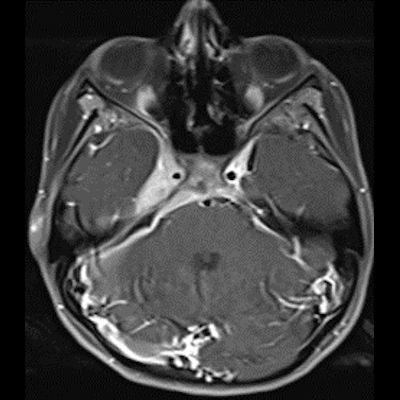

14 yaş, K

Baş ağrısı ve sağda abdusens felci

Neurosarcoidosis manifesting as cavernous sinus syndrome in systemic sarcoidosis

Sağ kavernoz sinüste kontrastlanan ICA yı çevreleyen daraltan yumuşak doku değerleri mevcuttur.Sağ parahiler bölgede lenfadenopati veya kitle lezyonu ile uyumlu olabilecek görünüm mevcuttur.Ayırıcı tanıda Nazofarink Ca metastazı,lenfoma,sarkaidoz,wegener granulomatozu düşünüle bilir.Çocuk hasta olduğu için daha çok lenfoma olarak düşündüm